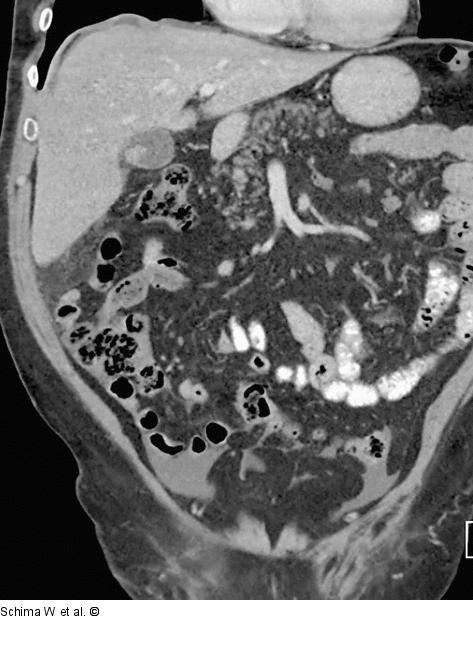

Abbildung 1: MDCT Die Kontrastmittel-verstärkte MDCT zeigt die zum Teil schalig wandverkalkte Mukozele der Appendix im rechten Unterbauch, welche von einer umschriebenen Flüssigkeitsansammlung (dem Pseudomyxoma) umgeben ist. Es zeigen sich auch noch weitere Retentionen im linken Unterbauch sowie perihepatisch-subphrenisch. |

Die Kontrastmittel-verstärkte MDCT zeigt die zum Teil schalig wandverkalkte Mukozele der Appendix im rechten Unterbauch, welche von einer umschriebenen Flüssigkeitsansammlung (dem Pseudomyxoma) umgeben ist. Es zeigen sich auch noch weitere Retentionen im linken Unterbauch sowie perihepatisch-subphrenisch. |